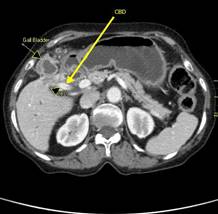

Компьютерная томография.

Среди методов, позволяющих получать изображения различных участков

человеческого тела, компьютерной томографии (КТ) отводится особая роль, а

именно роль стандарта.

Качество КТ-изображения, а значит и его

информативность, зависят от физических характеристик и особенностей строения

органа (плотности, концентрации электронов на единицу массы и других свойств

биологических тканей), а также от энергии используемого рентгеновского

излучения. Преимуществами КТ являются более высокое по сравнению с другими

методами визуализации разрешение по контрасту, возможность получить за короткое

время большое число поперечных проекций, что особенно ценно для локализации

области, из которой в дальнейшем берется проба ткани для биопсии, а также для

планирования хирургического вмешательства и последующей радиотерапии.

Ограничением метода КТ при исследованиях внутренних органов является отсутствие

возможности получать изображения от больших участков в продольных и фронтальных

проекциях. Этот недостаток можно преодолеть, используя в ходе исследования

специальные контрастные вещества.